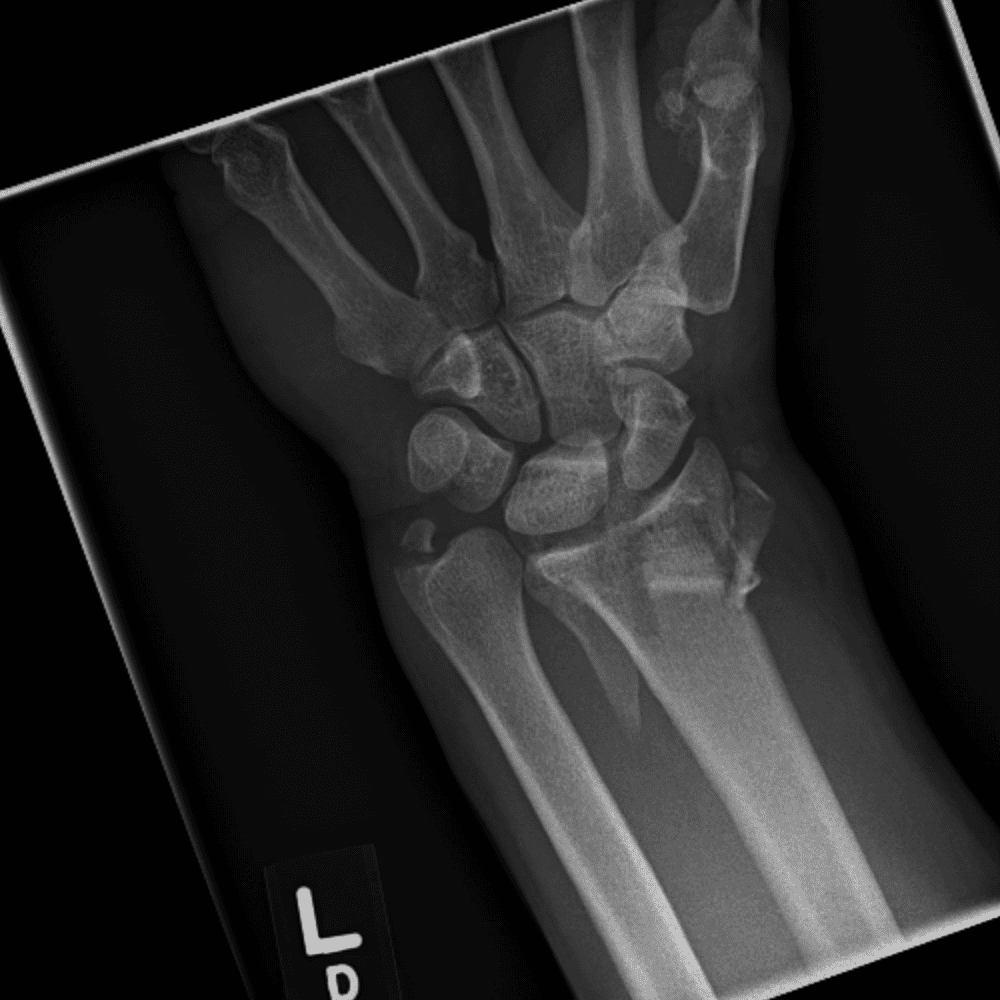

Simuliert den Dienst durch subtile oder schwierige Fälle und einige Normalbefunde.

30 Fälle